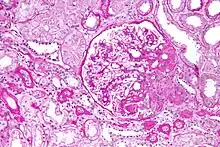

| Light micrograph of focal segmental glomerulosclerosis, hilar variant. Kidney biopsy. PAS stain. | |

On histology, FSGS manifests as scarring (sclerosis) to segments of glomeruli; moreover, only a portion of glomeruli are affected.[7][20][21] The focal and segmental nature of disease seen on histology help to distinguish FSGS from other types of glomerular sclerosis.[21]

Diagnosis of FSGS is made by renal biopsy that includes at least fifteen serial cuts with at least eight glomeruli.[32][33] Histologic features include sclerosis (scarring) of a portion (average: 15%) of the glomerular space, with only a portion of glomeruli manifesting any sclerosis.[33]